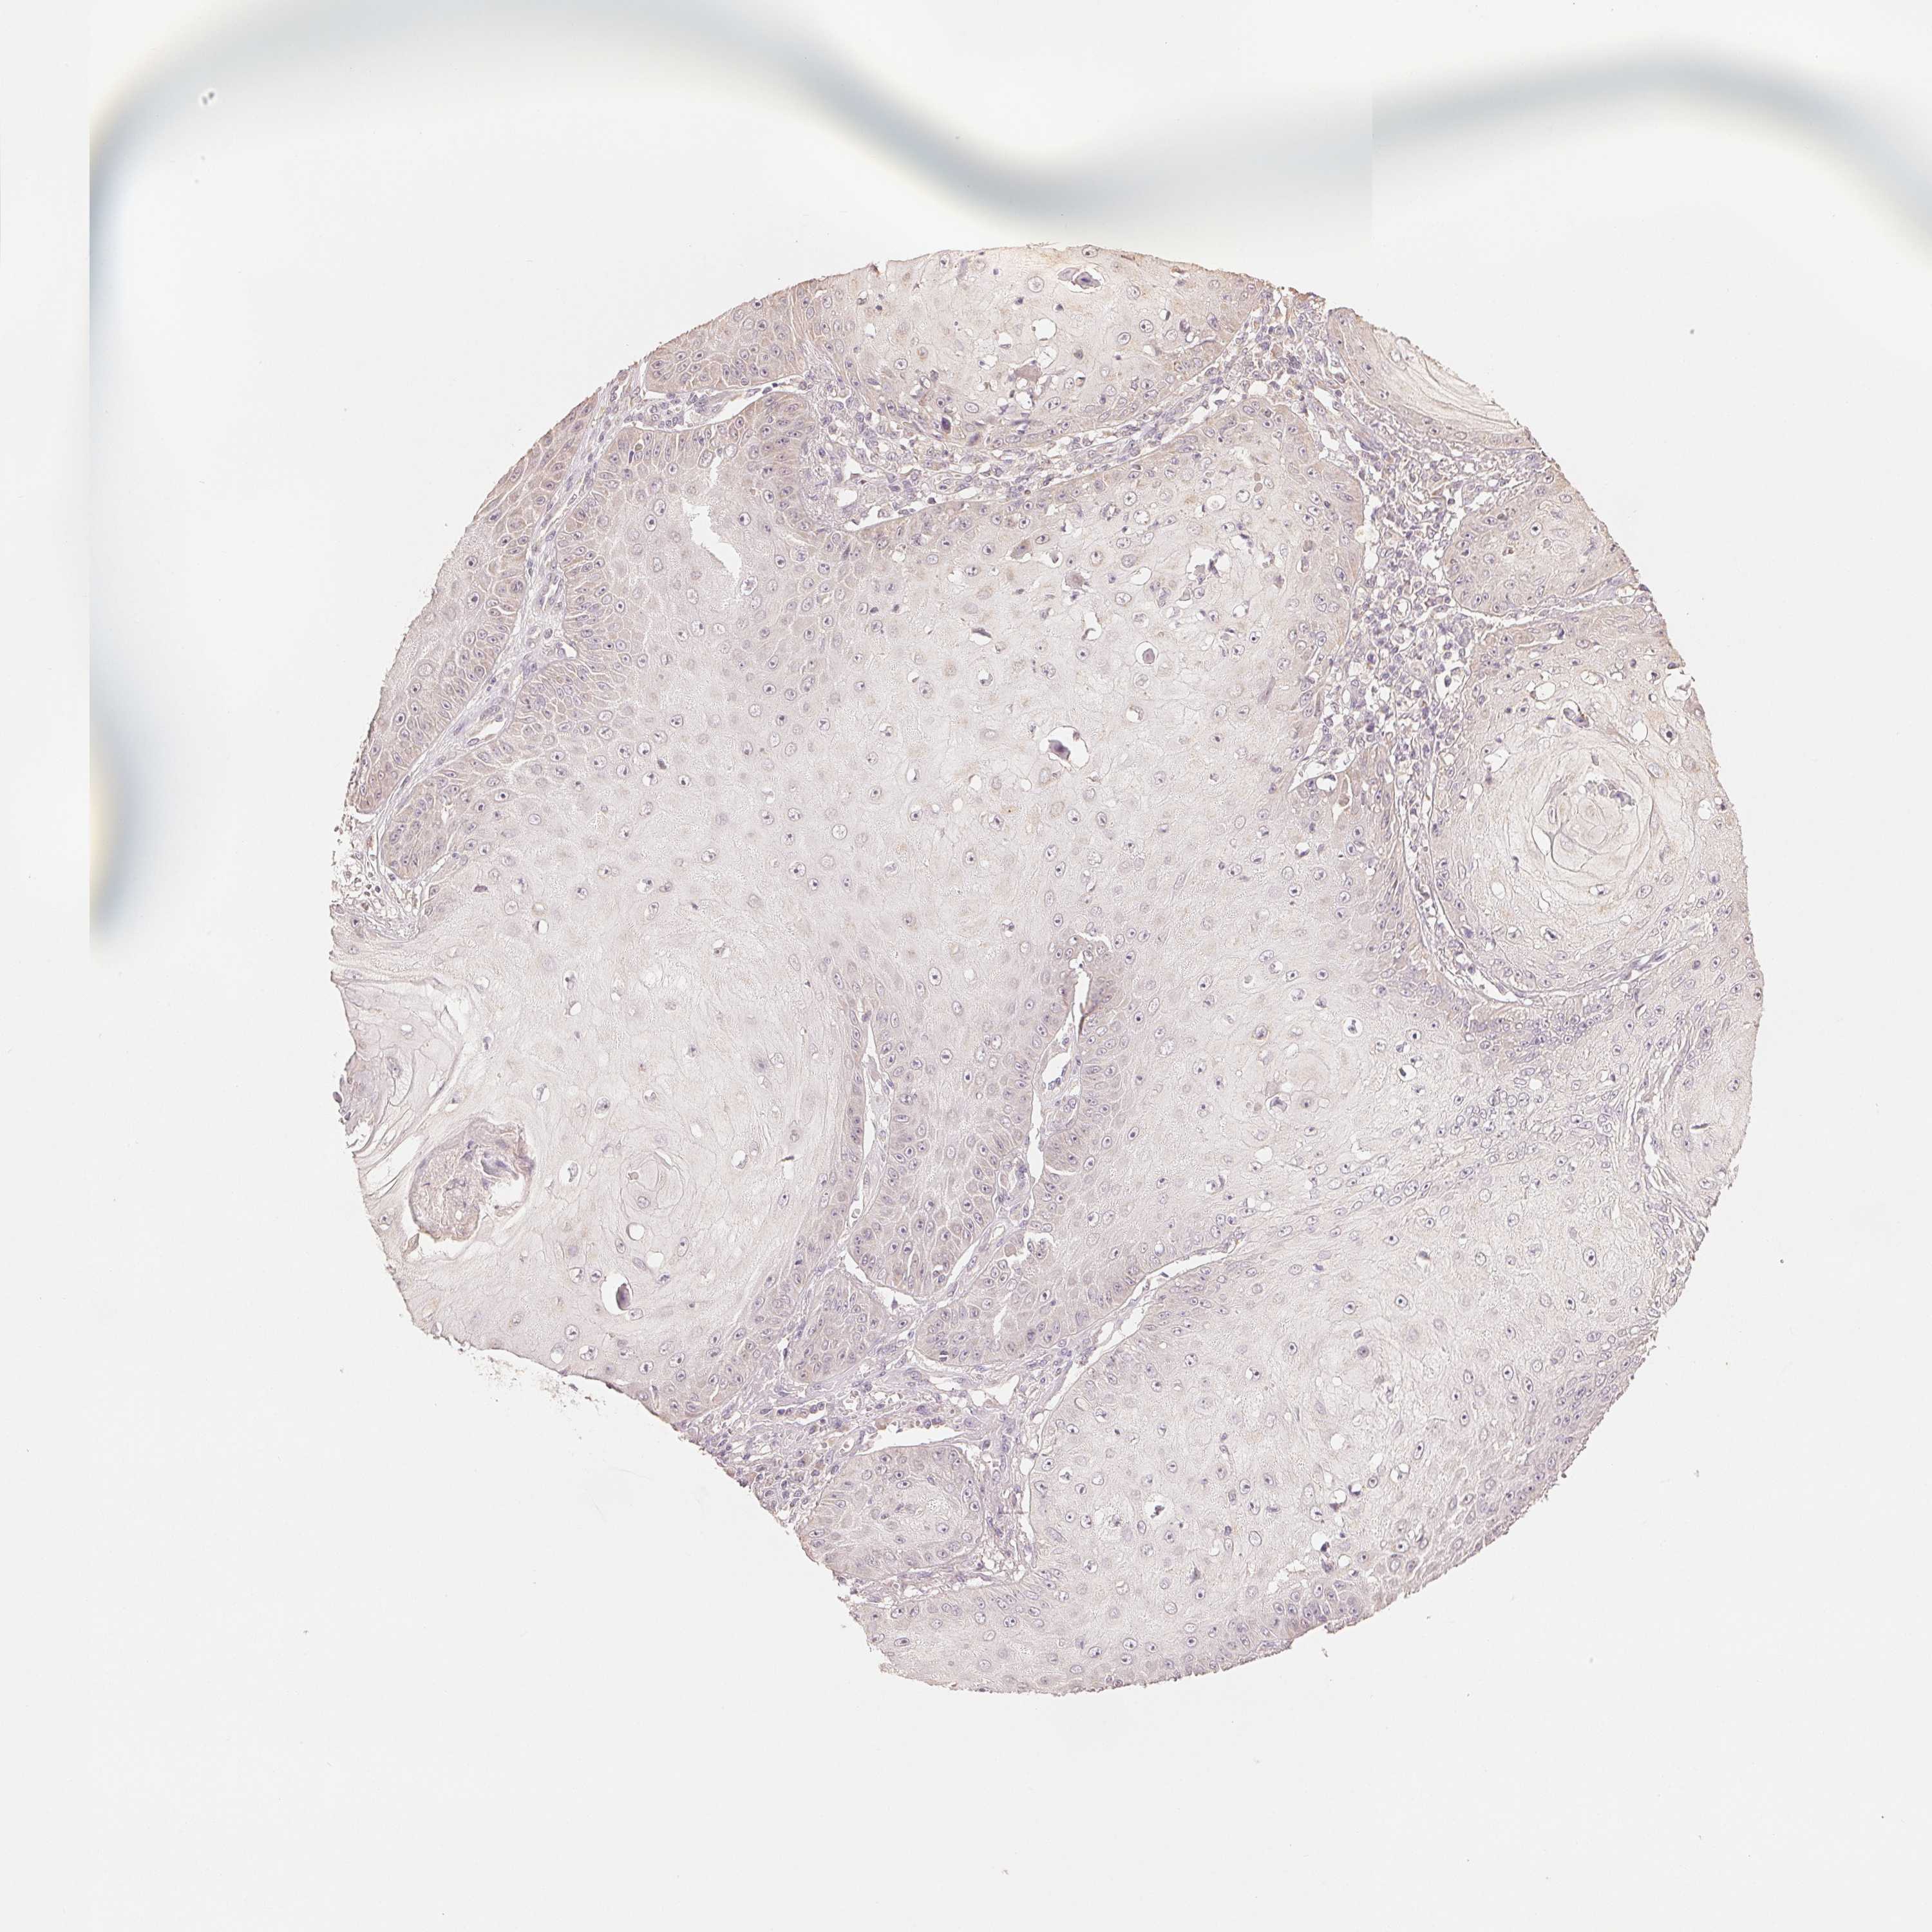

SKIN CANCER - Protein expressioni

A mouse-over function shows sample information and annotation data. Click on an image to view it in a full screen mode. Samples can be filtered based on level of antibody staining by selecting one or several of the following categories: high, medium, low and not detected. The assay and annotation is described here.

Antibody stainingi

Antibody staining in the annotated cell types in the current human tissue is reported as not detected, low, medium, or high, based on conventional immunohistochemistry profiling in selected tissues. This score is based on the combination of the staining intensity and fraction of stained cells.

Each image is clickable and will lead to virtual microscopy that enables deeper exploration of all samples and also displays staining intensity scores, fraction scores and subcellular localization as well as patient and tissue information for each sample.

Antibody HPA044618

Antibody HPA062014

Basal cell carcinoma

Squamous cell carcinoma, NOS

Squamous cell carcinoma, metastatic, NOS

BCC, high aggressive